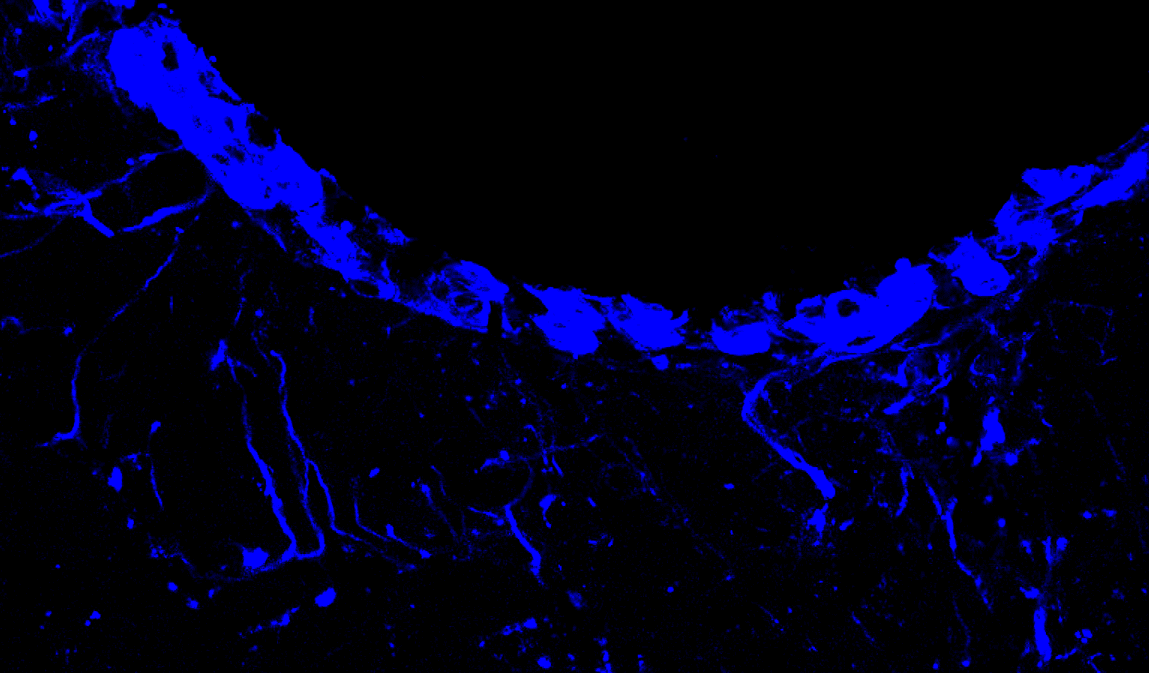

The prevalence of obesity has exploded over the past 40 years. The biological systems that underlie the excessive eating behavior contributing to obesity onset remain poorly understood. Our research goal is to discover the neural systems and psychological processes that control energy balance, with a particular focus on understanding the neurobiological substrates that regulate obesity-promoting behaviors such as food impulsivity, environmental cue-induced eating, and excessive meal size.

Another primary focus of our lab is to study how the brain is negatively impacted by dietary and metabolic factors. Consumption of Western diets (high in saturated fatty acids, sugars, and processed foods) not only contributes to obesity development, but also produces deficits in learning and memory capabilities and can even increase the risk for developing dementia. We are currently examining the specific causal dietary factors, critical developmental periods, and neurobiological mechanisms underlying diet-induced cognitive decline. Ongoing research identifies the gut microbiome as a critical link between unhealthy junk food diets and neurocognition.